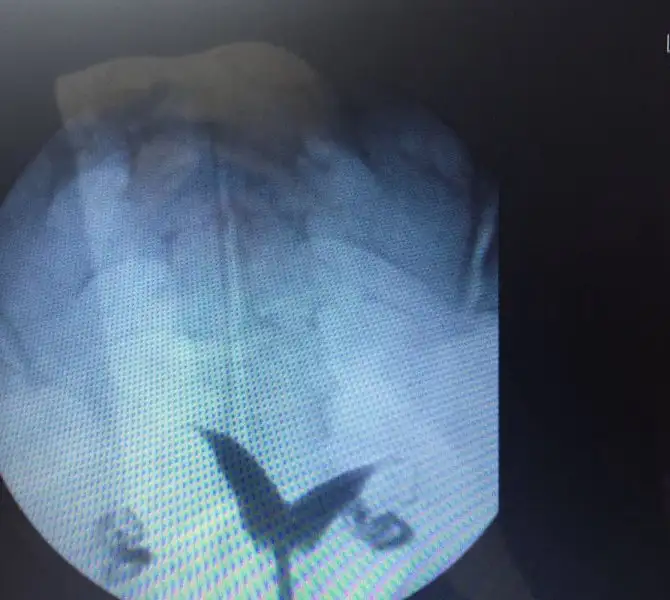

Yanımda olsa işte ellerimle besleyeceğim ama kavuşmamıza az kaldı Allah on izniyle perdenizin ameliyat olmadan önceki görüntüsü var mı acaba benimkine doktor derin değil dedi ama hiçte öyle durmuyor :S

Benimki bu şekilde seninkide buna benzer miydi?Hayir yok canim maalesef .